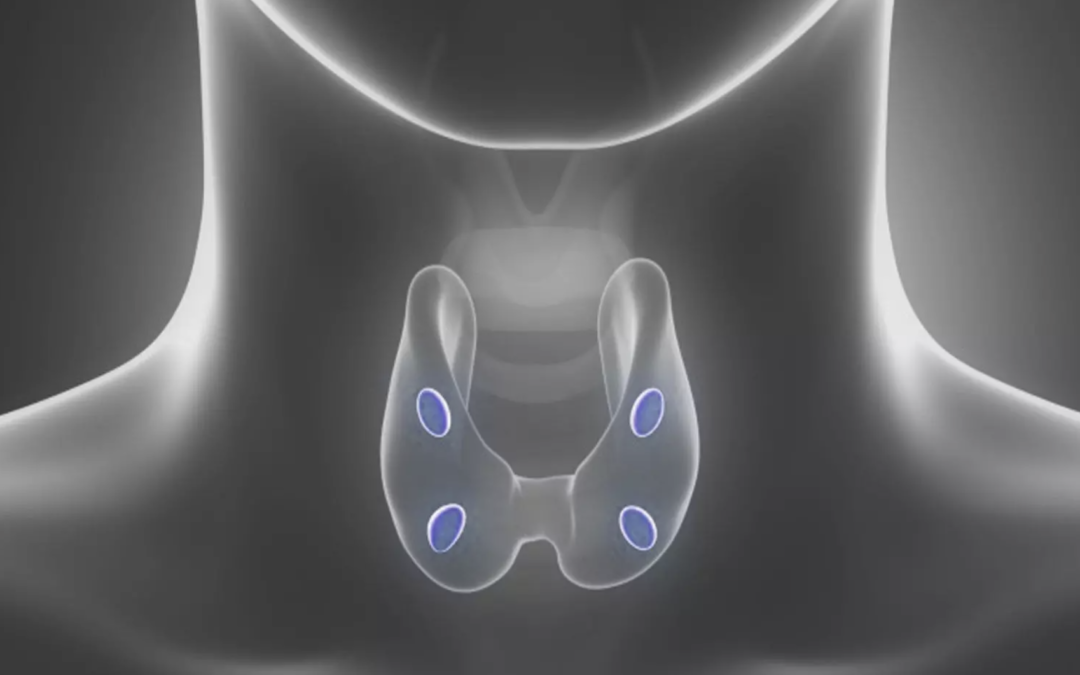

Αυτός είναι και ο λόγος που πρέπει να εξετάζονται και οι τέσσερις Παραθυρεοειδείς αδένες διεγχειρητικά ,έτσι ώστε να μην μείνει πίσω κάποιος παθολογικός.

Περίπου στο (5-10%) των ασθενών που πάσχουν απο πρωτοπαθή υπερπαραθυρεοειδισμό και οι τέσσερις Παραθυρεοειδείς αδένες είναι διογκωμένοι και παθολογικοί.

Η διάγνωση ,σε αυτή τη περίπτωση ,είναι «Υπερπλασία παραθυρεοειδών». Όλοι ,δηλαδή ,οι Παραθυρεοειδείς υπερπαράγουν παραθορμόνη.

Οι ασθενείς με υπερπλασία παραθυρεοειδών θα πρέπει να υποβληθούν σε «υφολική Παραθυρεοειδεκτομή» ,δηλαδή να αφαιρεθούν οι μεγαλύτεροι ,σε μέγεθος, Παραθυρεοειδείς αδένες και να μείνει μόνο ένα τμήμα του μικρότερου απο τους τέσσερις.